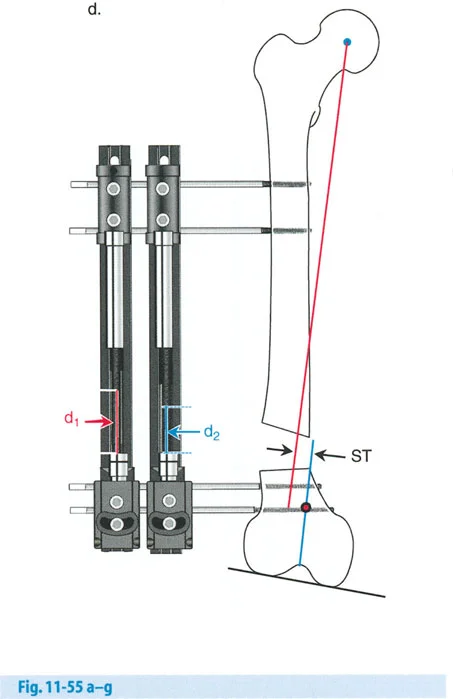

إتقان معدلات الشد: قاعدة المثلثات المتشابهة

القاعدة الذهبية البيولوجية لتوليد العظم بالشد، التي وضعها إليزاروف بعد عقود من التجارب على الحيوانات والبشر، هي معدل شد يبلغ 1 ملم يوميًا. يتم تقسيم هذا عادة إلى زيادات قدرها 0.25 ملم كل 6 ساعات لمحاكاة النمو المستمر للوحة النمو.

ومع ذلك، فإن الخطأ الشائع، الذي قد يكون كارثيًا أحيانًا للجراحين المبتدئين، هو سوء فهم أين يجب أن يحدث هذا الـ 1 ملم يوميًا.

معدل 1 ملم/يوم ينطبق بشكل صارم على القشرة المقعرة للعظم في موقع قطع العظم (الحافة الأمامية للإسفين المفتوح). نظرًا لأن الجهاز (قضيب الشد أو دعامة TSF) يقع على مسافة من العظم، خارج غلاف الأنسجة الرخوة، فإنه يتحرك على طول قوس أكبر بكثير. إذا وجهت المريض لشد القضيب بمعدل 1 ملم يوميًا، فإن العظم الفعلي سيُشد بجزء ضئيل من هذا المعدل، مما يؤدي إلى التصلب المبكر لموقع قطع العظم.

حساب معدل الشد الحقيقي

لحساب المعدل الصحيح للشد عند المفصلة، نستخدم قاعدة المثلثات المتشابهة، والتي تعتمد أساسًا على القاعدة الهندسية للدوائر متحدة